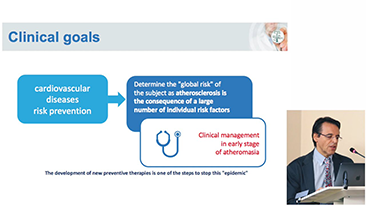

???19 - ??? ????? ?? ??

??? ????? ?? ??? ???? ??? ???? ??? ????, ?? ?? ??(PPE)? ??? ??, ? ??, ??? ?? ??? ???? ??? ?? ??? ??????. ???? ???? ??? ??? ??? ?? ??? ???? ?? ?? ?? ???? ?? ?? ??? ?? ???? ???? ?? ?? ?? ??(POC) ? ??? ??? ? ? ?????.